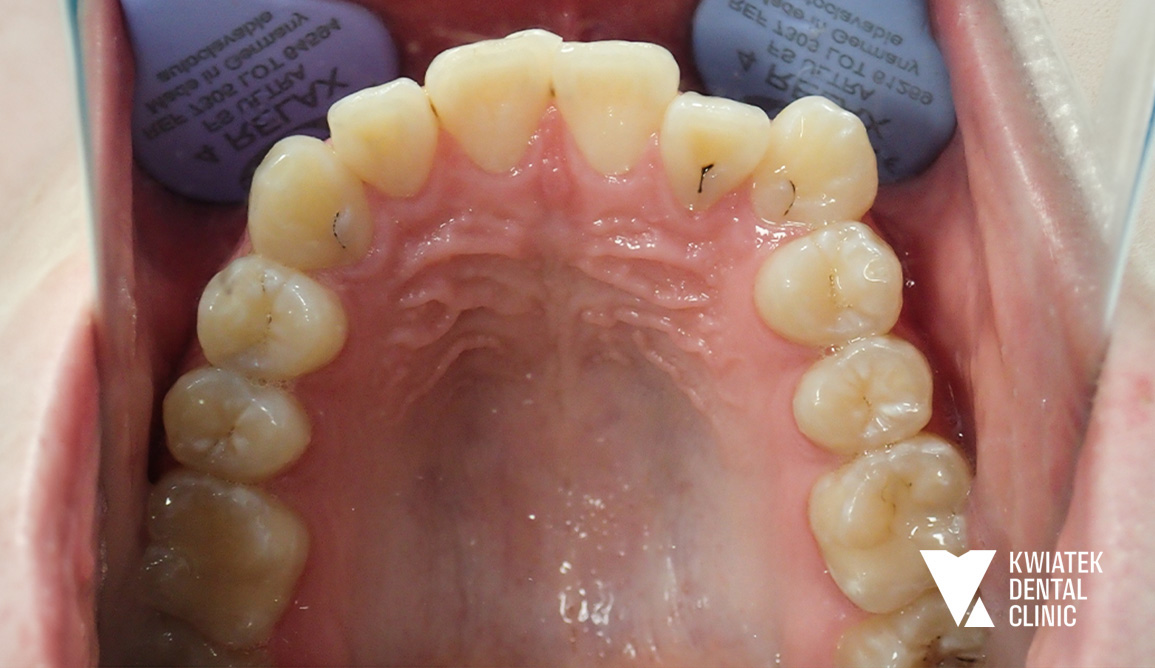

PRZED

Badanie kliniczne wykazało:

• I klasę Angle’a po obu stronach

• tendencję do kontaktu guzkowego na kłach po stronie prawej

• zgryz krzyżowy zęba 12

• znaczny deficyt miejsca dla zębów 12 i 13

• wychylenie przedsionkowe zęba 13

• płytki nagryz pionowy